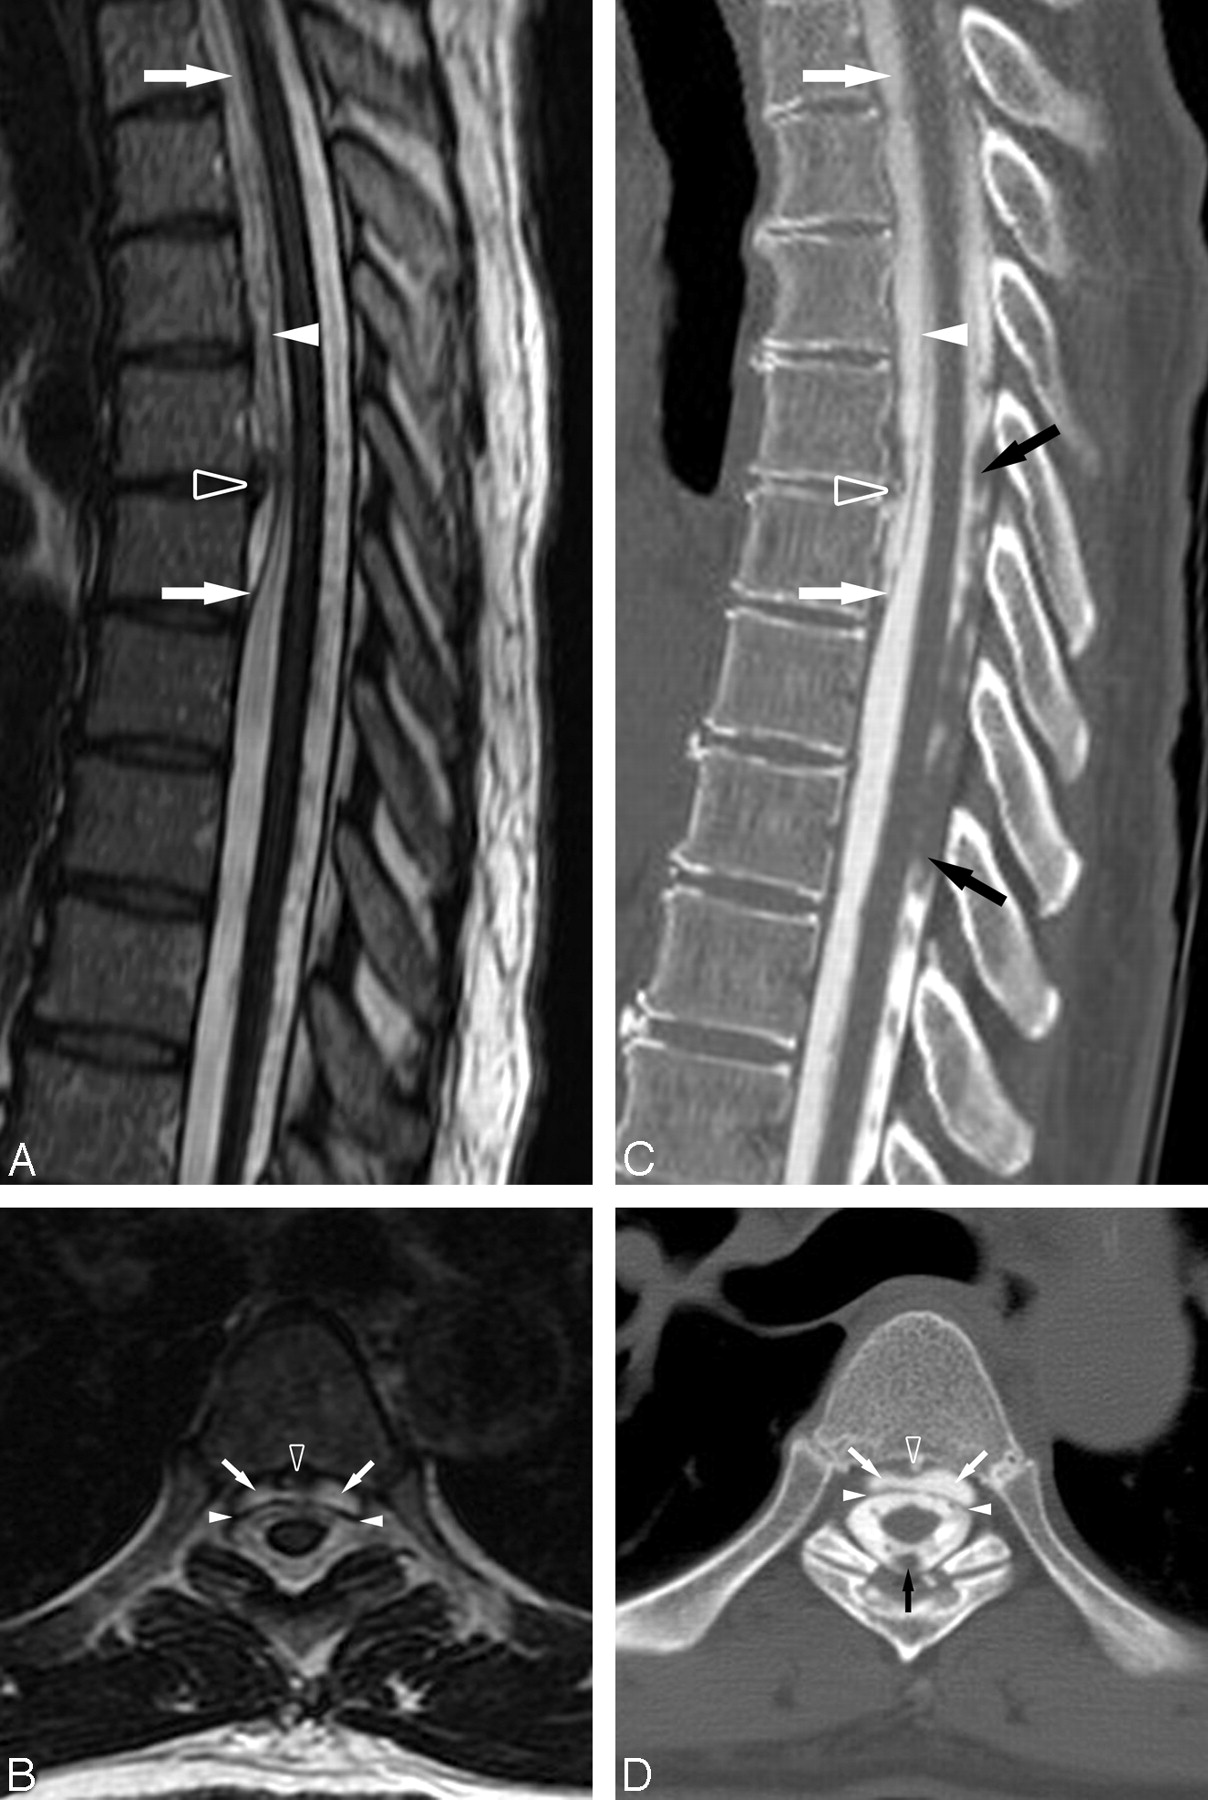

MR imaging of the brain and entire spine revealed prominent T2 shortening along the surface of the cerebellum, brain stem, and spinal cord consistent with susceptibility from hemosiderin deposition. A nonenhancing ventral epidural spinal fluid collection extended from the inferior aspect of C4 through the T6–T7 disk space (Figs 1A, -B). Moreover, a T2 hypointense fluid-fluid level suggestive of blood products was layering dependently in the distal thecal sac (not shown).

A, Sagittal T2-weighted (TR, 3300 msec; TE, 100.8 msec) image of the thoracic spine defines the caudal aspect of the epidural fluid collection at T6–T7. A prominent central disk extrusion is present at T5–T6. B, Axial T2-weighted (TR, 2600 msec; TE, 103.1 msec) image through the T5–T6 disk extrusion further delineates the ventral epidural fluid collection displacing the dura posteriorly. Note the prominent T2 hypointensity on the cord surface secondary to superficial siderosis. C, D, Postmyelography CT images in similar planes and at analogous levels to the MR images demonstrate that the ventral epidural fluid collection is opacified by intrathecal contrast to a degree similar to CSF within the thecal sac, confirming the presence of an active CSF leak. The prominent T5–T6 disk extrusion is partially calcified. Ventral epidural fluid collection (white arrows), dura (white arrowheads), T5–T6 disk extrusion (open arrowhead), and subarachnoid clot (black arrows) are shown.

Because the patient's presumptive diagnosis was superficial siderosis secondary to bleeding from a dural tear, a routine myelogram was performed via lumbar puncture, and postmyelography CT of the entire spine was obtained (Figs 1C, -D). The diffuse contrast opacification of the ventral epidural fluid collection confirmed the presence of a CSF leak. Subsequently, a dynamic CT myelogram was performed (not shown) by use of previously published methodology,1 but the site of the dural tear was not adequately localized because the rapid nature of the CSF leak resulted in a significant amount of contrast extending within the epidural fluid collection over 5 vertebral levels (T2–T6).